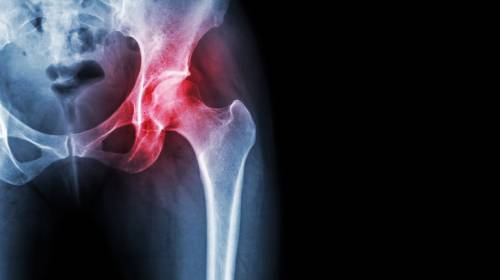

髖關(guān)節(jié)炎是如何引起的?【廣東高尚醫(yī)學(xué)影像】

髖關(guān)節(jié)屬于杵臼關(guān)節(jié),是由股骨頭和髖臼相對構(gòu)成,多為軸性關(guān)節(jié),能作屈伸、收展、旋轉(zhuǎn)等運(yùn)動(dòng),但由于關(guān)節(jié)頭和關(guān)節(jié)窩之間的面積差不大,運(yùn)動(dòng)范圍較小,且關(guān)節(jié)囊較厚,限制關(guān)節(jié)運(yùn)動(dòng)幅度的韌帶又比較有力,因此髖關(guān)節(jié)雖有強(qiáng)穩(wěn)固性,但靈活性卻較差,因此在髖關(guān)節(jié)運(yùn)動(dòng)時(shí),若有外力作用于膝關(guān)節(jié),就容易導(dǎo)致髖關(guān)節(jié)后脫位。當(dāng)髖關(guān)節(jié)面長期負(fù)重不均衡,關(guān)節(jié)軟骨就會(huì)產(chǎn)生變性(或產(chǎn)生骨質(zhì)結(jié)構(gòu)改變),這就是髖關(guān)節(jié)炎。

X線篩查對髖關(guān)節(jié)炎的判斷:

1. 早期影像顯示髖關(guān)節(jié)周圍軟組織腫脹,密度增加,關(guān)節(jié)間隙增寬。

2. 中期影像顯示為關(guān)節(jié)軟骨遭破壞,關(guān)節(jié)間隙變窄,關(guān)節(jié)面骨質(zhì)出現(xiàn)糜爛破壞。

3. 后期影像顯示化膿病變從關(guān)節(jié)囊韌帶附著處入侵骨內(nèi),骨內(nèi)形成膿腫。